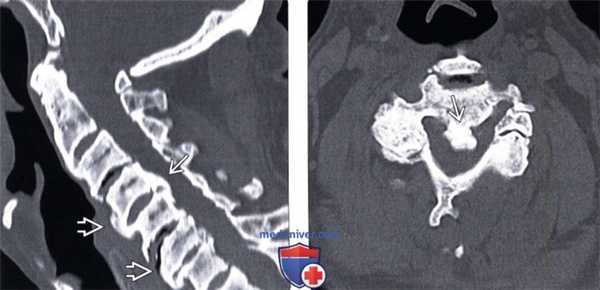

(Слева) КТ, сагиттальный срез: фокальный тип ОЗПС, ограниченной преимущественно уровнями межпозвонковых дисков, в сочетании с ДИСГ.

(Справа) КТ, аксиальный срез: участок массивной оссификации ЗПС, выступающей в просвет спинномозгового канала со значительным его стенозированием.в) Дифференциальная диагностика: